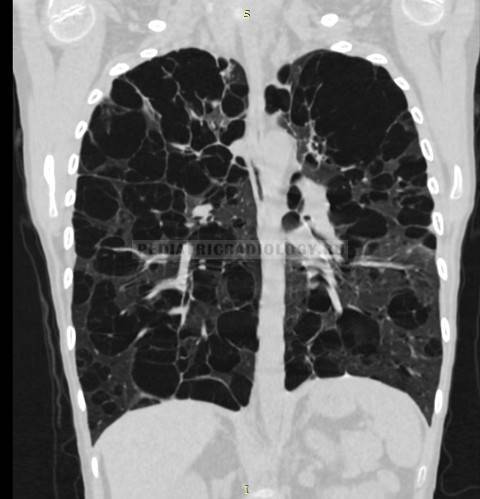

- Хаотично расположенные очаги. Такие образования характерны для патологических гематогенных процессов. Это может быть гематогенная инфекция, туберкулёз или метастазы гематогенного типа. Большие множественные очаги, размером около 10 мм, частенько наблюдаются при септических эмболиях, гранулематозе, грибковых инфекциях и метастазах. Все эти заболевания имеют некоторые отличия, по которым их можно дифференцировать.

Патологические очаги бывают плотными, средней плотности, а также рыхлыми. Если в лёгких наблюдаются единичные уплотнения, то это может быть как возрастным изменением, которое не представляет опасности для человека, так и опасным заболеванием. Если наблюдаются множественные очаги, то здесь речь идёт о воспалении лёгких, туберкулёзе или редких формах онкологических заболеваний.